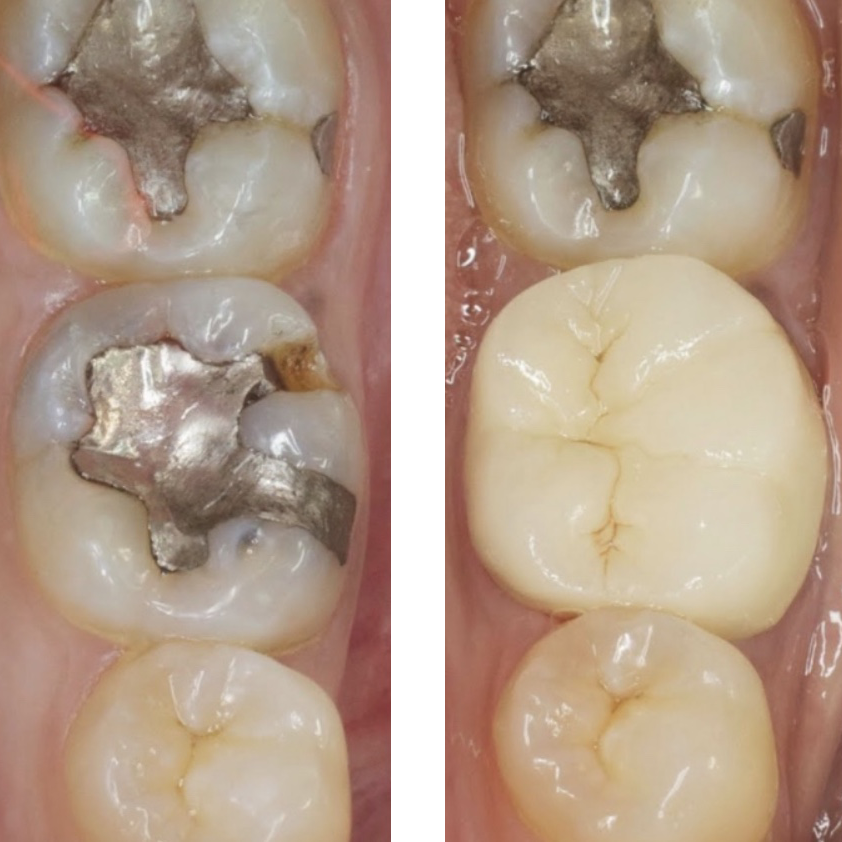

Intra Oral Photography

The intraoral camera is tiny pin hole camera on a wand that allows us to take pictures of your teeth, then instantly display the image on the chair-side monitor. This allows us to show you exactly what we see. Subsequent pictures will show us changes that occur over time, such as the picture shown on the right.